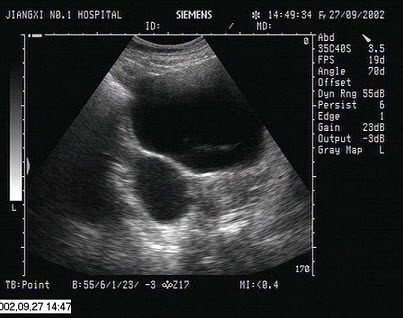

男,56岁,上腹经常疼痛不适多年。结合超声声像图,诊断为()

A.胆囊多发性胆固醇结晶

B.胆囊多发性息肉

C.胆囊多发性结石

D.胆囊癌

E.胆泥淤积